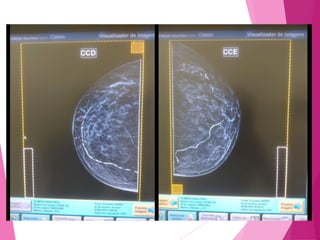

MAMOGRAFIA

DIGITAL

Vantagens:

 Custos

operacionais

 Opções de

arquivamento e

PACS

 Manipulação da

imagem

COMPARATIVO

DIGITAL VS. FILME